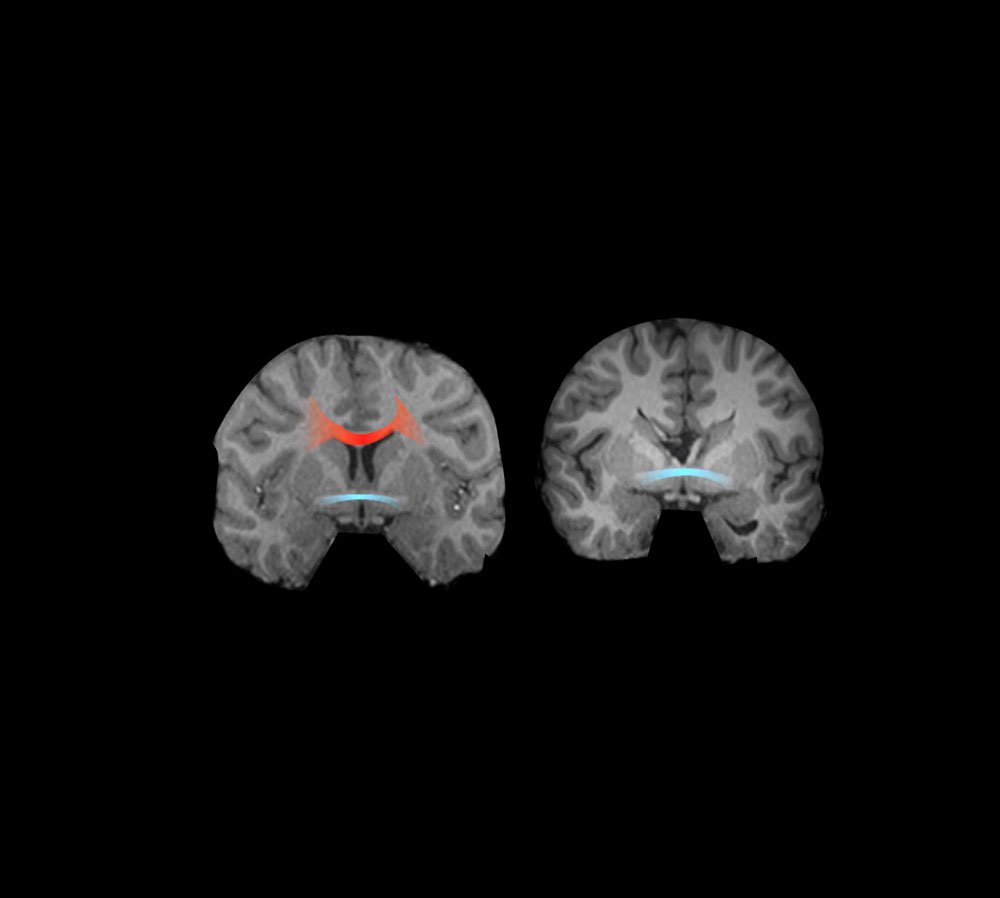

The corpus callosum is the largest connection in the human brain, connecting the left and right brain hemispheres via about 200 million fibers. In very rare cases it is surgically cut to treat epilepsy—causing the famous "split-brain" syndrome, for whose discovery the late Caltech professor Roger Sperry received the Nobel Prize. People with AgCC are like split-brain patients in that they are missing their corpus callosum—except they are born this way. In spite of this significant brain malformation, many of these individuals are relatively high-functioning individuals, with jobs and families, but they tend to have difficulty interacting with other people, among other symptoms such as memory deficits and developmental delays. These difficulties in social behavior bear a strong resemblance to those faced by high-functioning people with autism spectrum disorder.

According to Adolphs, it is important to note that AgCC can now be diagnosed before a baby is born, using high-resolution ultrasound imaging during pregnancy. This latest development also opens the door for some exciting future directions in research.

"If we could follow a baby with AgCC as it grows up, and visualize its brain with MRI each year, we would gain such a wealth of knowledge," Adolphs says.